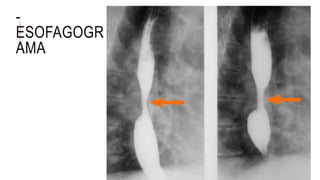

-

ESOFAGOGR

AMA